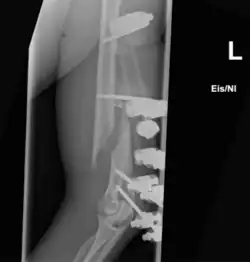

- Die winkelstabile Platte am proximalen Humerusschaft

-

Eine Fraktur am oberen Ende des Humerus -

Versorgung mit winkelstabiler Platte -

Ansicht in anderer Ebene